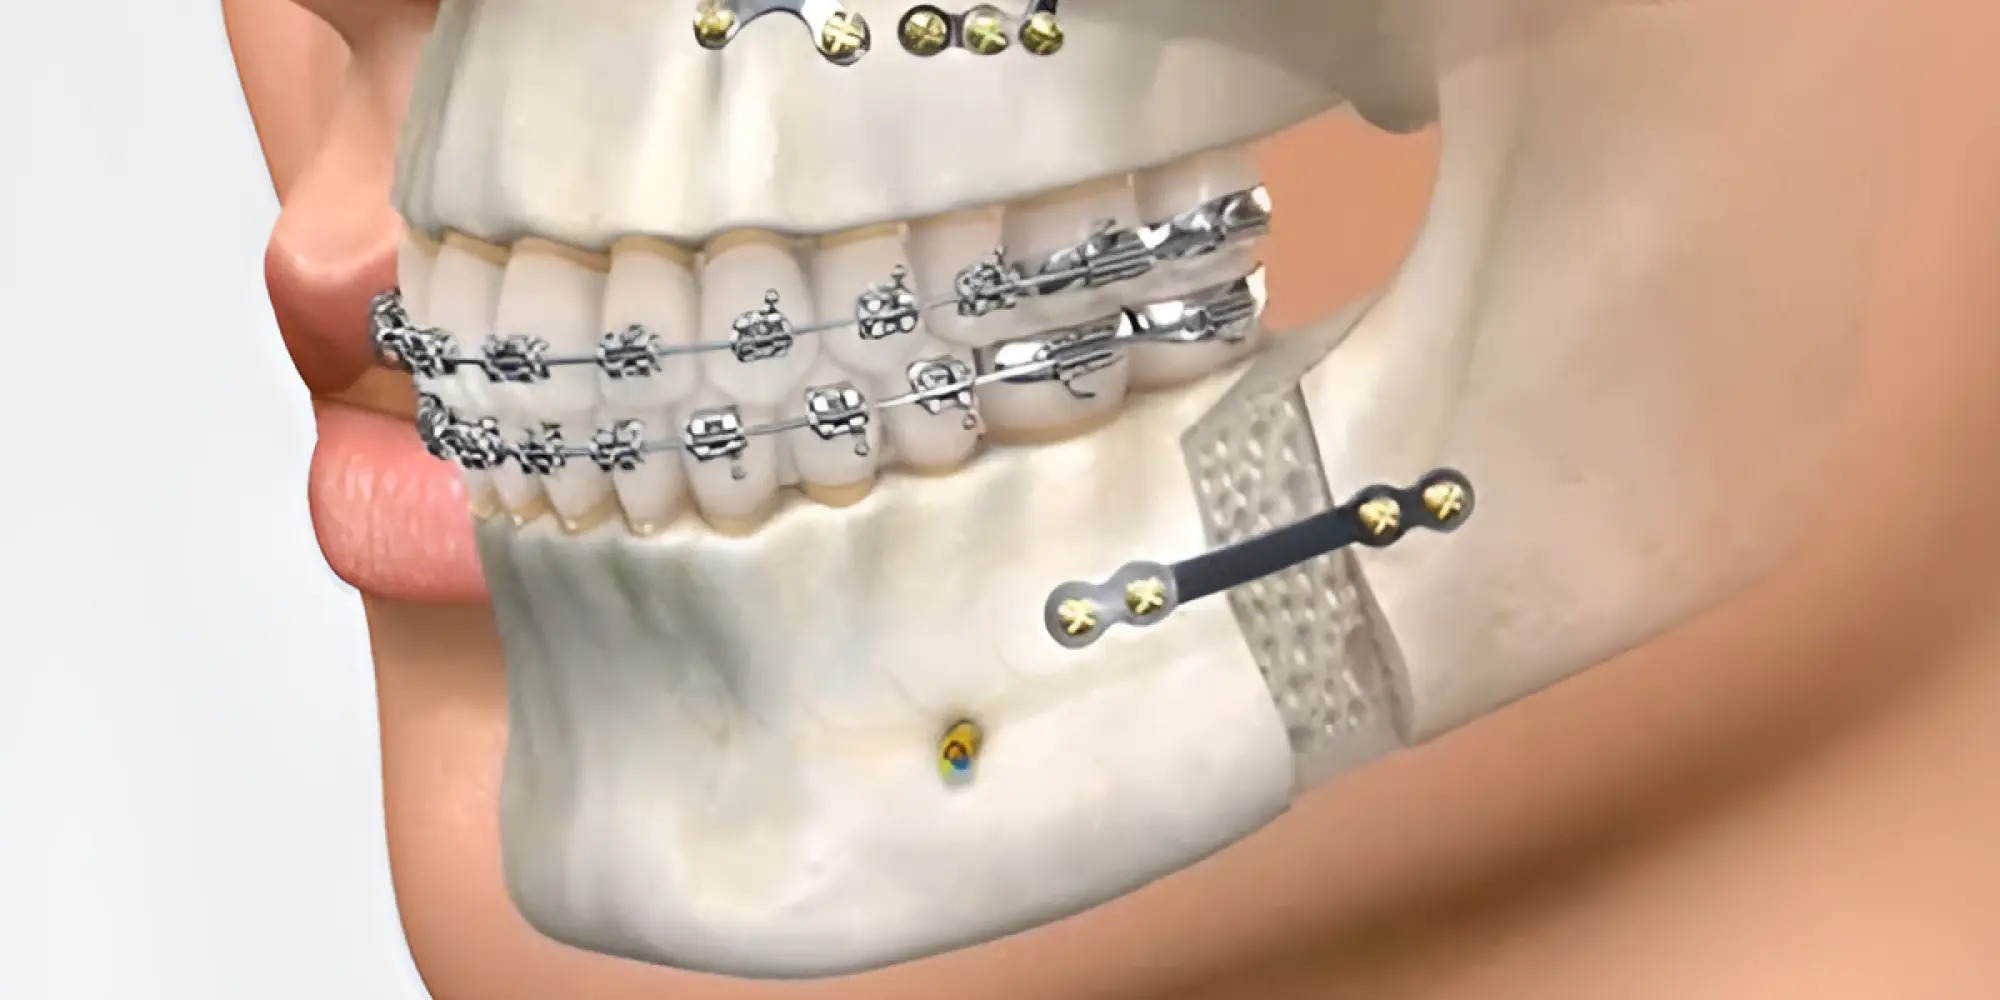

A Cirurgia e Traumatologia Bucomaxilofacial (CTBMF) é uma especialidade odontológica complexa e abrangente que se dedica ao diagnóstico e tratamento cirúrgico de doenças, lesões, anomalias congênitas e adquiridas que afetam a boca, os maxilares (maxila e mandíbula), a face e as estruturas anexas, como a articulação temporomandibular (ATM). O cirurgião bucomaxilofacial possui um conhecimento aprofundado da anatomia dessa região, estando apto a realizar desde procedimentos mais simples em consultório até cirurgias de grande porte em ambiente hospitalar.

- Tratamento de algumas deformidades dentofaciais menos complexas ou como parte de um planejamento orto-cirúrgico.